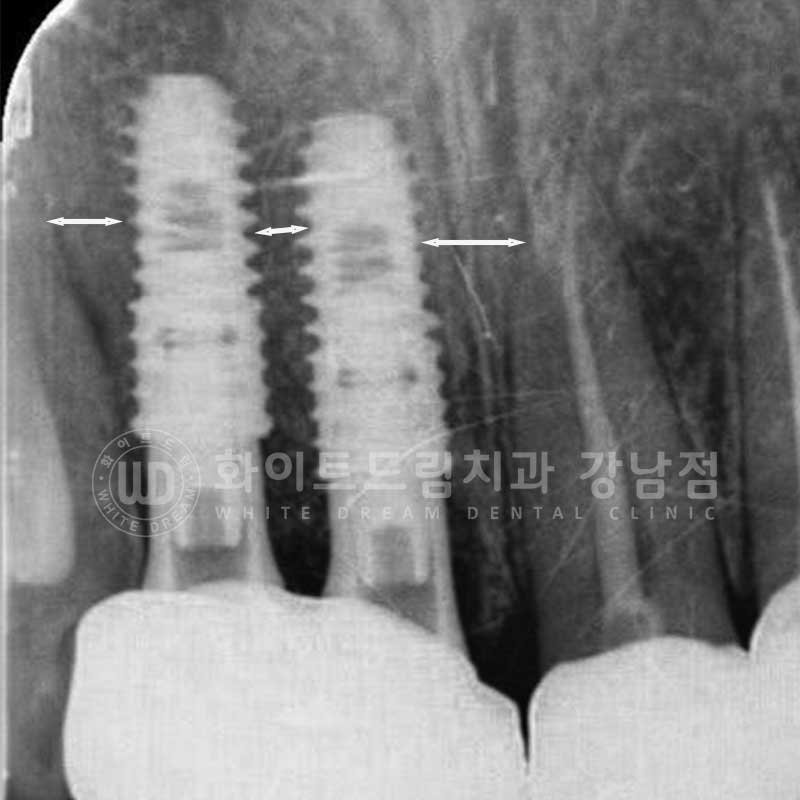

또한 치아 사이, 간격이 좁은 부위에 임플란트를 식립할 때는

인접치와 어느 정도 거리를 두고 식립해야 하는데요.

인접치의 치근과 최소 1.5mm의 거리를 확보한 후 식립해야

인접치의 손상과 합병증을 예방할 수 있는데요.

인접치와 임플란트가 과도하게 가까우면

임플란트가 감염되거나 골흡수 등의 이유로 실패하거나

단기간 내 임플란트가 흔들리거나 주위 염증이 발생해 제거하게 되는 문제가 발생할 수 있습니다.

인접치는

치주 인대와 주변조직의 상실이 일어나 치아의 생활력을 상실하거나 치근단염, 치근흡수 등이

발생할 수 있답니다.

▲ 환자분의 식립 후 치근단 사진

인접치와 임플란트 사이 일정 공간을 확보하여 잘 식립된 것이 확인됩니다.